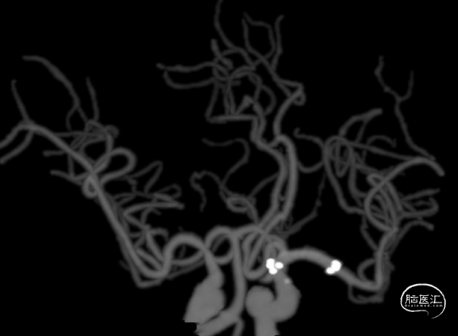

造影示左侧大脑中动脉M1段闭塞,病变呈笔尖样,大脑前动脉通过软膜支向大脑中动脉部分代偿,ASITN/SIR:3级。

200cm 0.014in 微导丝配合10系微导管越过病变,回退微导管,造影证实微导丝位于真腔,首过效应阳性,局部见重度狭窄,狭窄后见血栓形成。

选择2.25×15mm SacSpeed®球囊扩张导管,4atm扩张后,跟进5F 125cm 中间导管至球囊近端。

造影见M1段局部重度狭窄,远端血流通畅,再予6atm扩张后M1段狭窄较前改善,远端血流通畅。

观察15分钟后,见M1段见弹性回缩,局部病变及远端血流稍缓慢。

植入4.0×23mm闭环支架,支架植入后血流恢复,mTICI 3级。

术后造影左侧大脑中动脉M1段支架成形良好,未见明显残余狭窄,mTICI 3级。